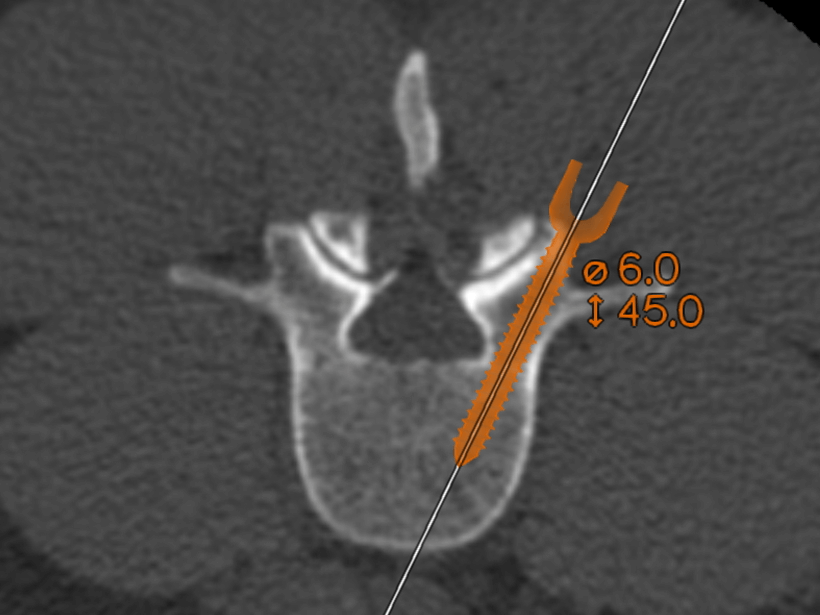

Brainlab LoopX Mobile Imaging Robot and Cirq Robotic Alignment Module